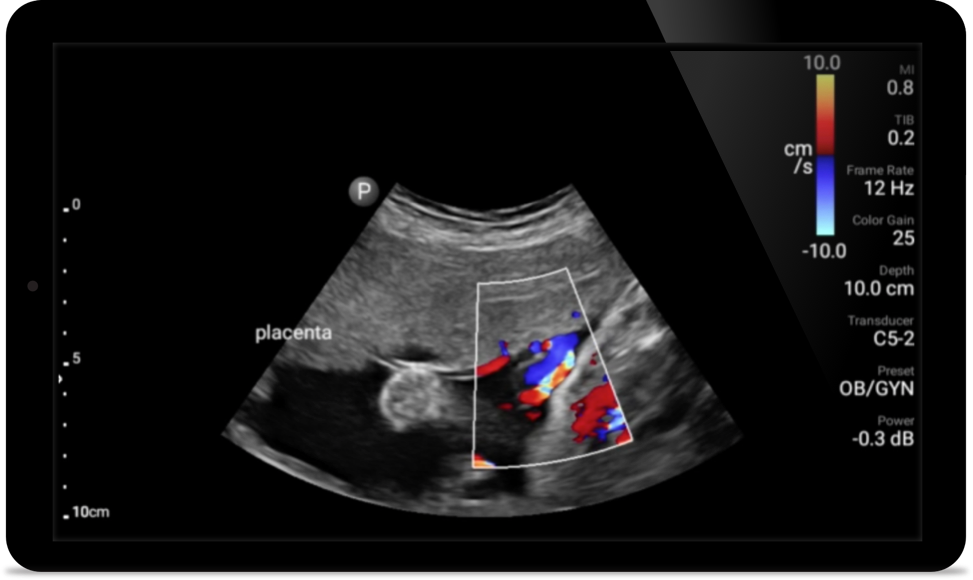

Get the clarity of larger ultrasound systems with Lumify

SonoCT reinforces real tissue imaging while eliminating random artifacts. This technology produces images superior to conventional imaging in up to 94% of patients.

• 5 to 2 MHz extended operating frequency range • 50mm radius of curvature • 2D, color Doppler, M-mode, advanced XRES and multivariate harmonic imaging, SonoCT • High-resolution imaging for deeper applications: abdominal, gall bladder, OB/GYN and lung imaging preset optimizations